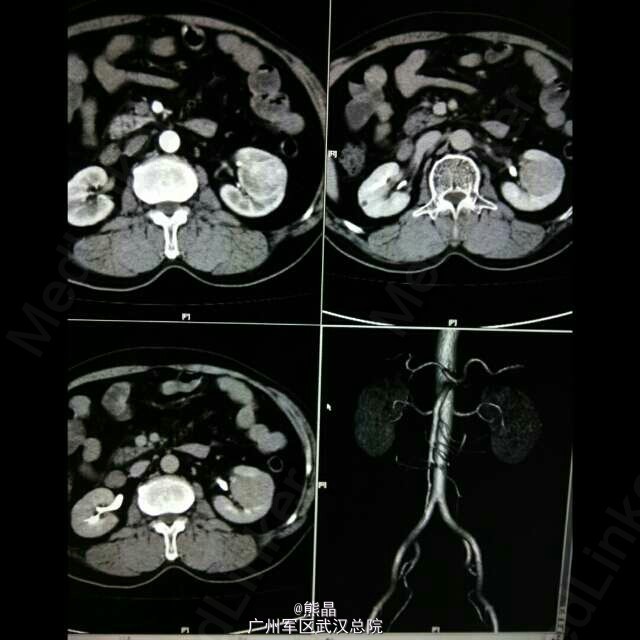

患者男性,61岁,体检发现左肾占位病变5天,无明显临床症状。 肾脏嗜酸性细胞瘤是一种少见的肾脏良性肿瘤,与肾癌鉴别较困难。 肾脏嗜酸性细胞瘤增强扫描可以出现轮辐状强化,是其特征之一,肿瘤中可见星状瘢痕,为纤维母细胞增生,如肿瘤中有钙化,可以除外嗜酸。